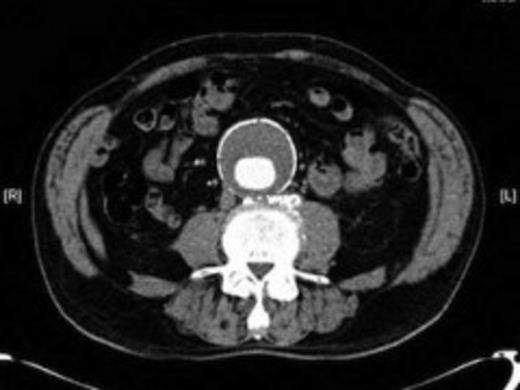

An 82 year old gentleman with known peripheral vascular disease and previous open popliteal aneurysm repair underwent endovascular repair of a 58mm infrarenal abdominal aortic aneurysm (Fig. 1) using a Cook Zenith bifurcated prosthesis The Zenith Flex® AAA Endovascular Graft (Cook Medical Inc., Bloomington, USA). The operation, which was performed under general anaesthetic and bilateral groin cut downs with intravenous prophylactic antibiotic cover on induction (Co-amoxiclav 1.2g) was uneventful. The main body was deployed via the right side. Completion angiograms showed satisfactory exclusion of the aneurysm sac with good graft position and no endoleaks. Post operatively the patient had a brief period of low grade pyrexia and lower abdominal pain that settled spontaneously. This was thought to be due to post implant graft reaction. Pre-discharge imaging with plain abdominal X-rays was deemed satisfactory.